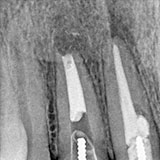

実際の治療例です。

真ん中の歯の頭が黒くなっており、むし歯が歯の中にある黒い線の神経の部屋まで到達していました。そこでむし歯を取り除き、神経の部屋の清掃を行い、薬で封鎖しました。

白く写る薬が根の先まで到達していますが、根の先で神経が枝分かれしているのが見て取れます。

この薬を根の先までしっかり入れることで細菌が増えるのを防ぎます。

他にも写真の様に根の先端は複雑な形をしています。